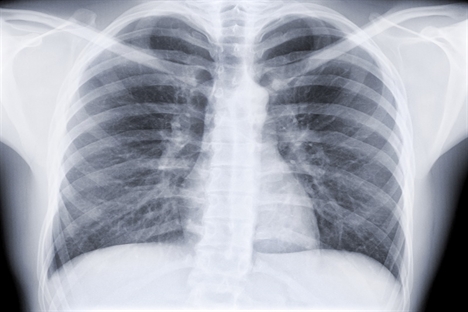

Lung cancer surgery boosts survival rates

Surgery is offering lung cancer patients a better chance of survival, the latest audit shows. The National Lung Cancer Audit 2012 found that the use of surgery as treatment for common lung cancers has increased by nearly 60% over the last five years, with the median average survival time up by 16% over that time.

When non-small cell lung cancer is caught early enough, surgery offers the best chance of a cure. Just over half of the 40,200 patients covered by the audit had this type, with 22% of those having surgery as part of their treatment. In 2008, the proportion was 14%.

Survival has increased from 2008 to 221 days in 2012, with 55% of patients surviving six months and 39% a year. While regional variation in treatment remains, differences are narrowing on some measures, the audit suggests.